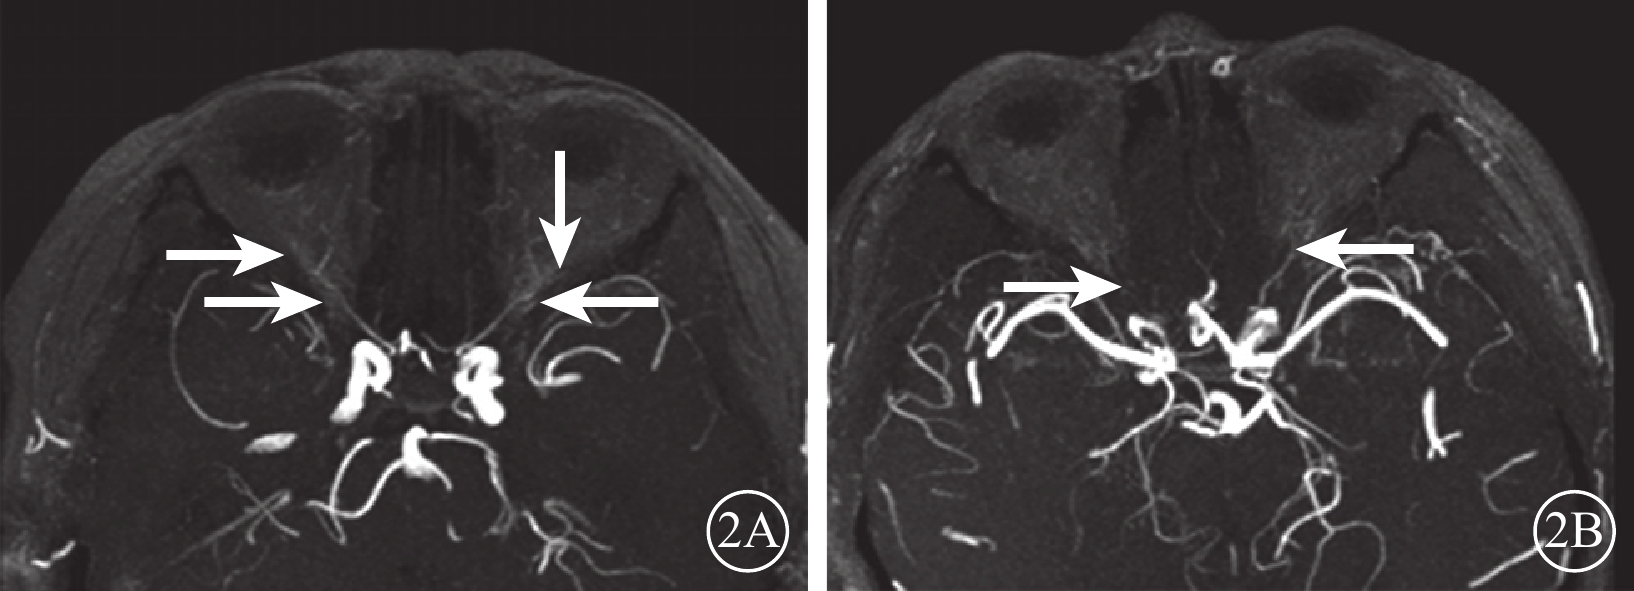

DR組72只眼中,眼動脈MRA 0級28只眼(38.9%);Ⅰ級28只眼(38.9%),其中眼動脈主干及其主要分支(鼻背動脈和淚腺動脈)顯影淺淡、外形變硬(圖2A)12只眼,眼動脈主干顯影正常、分支顯影中斷或不顯影14只眼;Ⅱ級16只眼(22.2%),其中眼動脈狹窄、僵硬伴分支顯影淺淡10只眼,分支顯影中斷或不顯影(圖2B)4只眼,眼動脈主干及其主要分支均不顯影2只眼。行CTA檢查的24只眼中,0級13只眼;Ⅰ級6只眼,其中眼動脈主干及其主要分支(鼻背動脈和淚腺動脈)顯影淺淡、管壁變硬(圖3A)4只眼,眼動脈主干顯影正常、分支不顯影2只眼;Ⅱ級5只眼,其中眼動脈主干伴分支明顯狹窄、僵硬(圖3B)3只眼,表現為眼動脈主干顯影分支不顯影2只眼。DR組眼動脈MRA、CTA分級一致性分析,Kappa值=0.86,一致性極強(表1)。DR組眼動脈MRA與對照組眼動脈MRA不同分級眼數比較,差異有統計學意義(Z=?5.74,P=0.000)。

圖2

DR患者MRA像。2A. MRAⅠ級,雙側眼動脈主干及其主要分支(鼻背動脈和淚腺動脈)顯影淺淡,走形稍僵直(白箭);2B. MRAⅡ級,右側眼動脈主干可見細線樣顯影,其分支鼻背動脈及淚腺動脈未見明確顯示,左側眼動脈主干顯影纖細淺淡,分支鼻背動脈及淚腺動脈顯示不清(白箭)

圖2

DR患者MRA像。2A. MRAⅠ級,雙側眼動脈主干及其主要分支(鼻背動脈和淚腺動脈)顯影淺淡,走形稍僵直(白箭);2B. MRAⅡ級,右側眼動脈主干可見細線樣顯影,其分支鼻背動脈及淚腺動脈未見明確顯示,左側眼動脈主干顯影纖細淺淡,分支鼻背動脈及淚腺動脈顯示不清(白箭)

DR組72只眼中,眼動脈MRA 0級28只眼(38.9%);Ⅰ級28只眼(38.9%),其中眼動脈主干及其主要分支(鼻背動脈和淚腺動脈)顯影淺淡、外形變硬(圖2A)12只眼,眼動脈主干顯影正常、分支顯影中斷或不顯影14只眼;Ⅱ級16只眼(22.2%),其中眼動脈狹窄、僵硬伴分支顯影淺淡10只眼,分支顯影中斷或不顯影(圖2B)4只眼,眼動脈主干及其主要分支均不顯影2只眼。行CTA檢查的24只眼中,0級13只眼;Ⅰ級6只眼,其中眼動脈主干及其主要分支(鼻背動脈和淚腺動脈)顯影淺淡、管壁變硬(圖3A)4只眼,眼動脈主干顯影正常、分支不顯影2只眼;Ⅱ級5只眼,其中眼動脈主干伴分支明顯狹窄、僵硬(圖3B)3只眼,表現為眼動脈主干顯影分支不顯影2只眼。DR組眼動脈MRA、CTA分級一致性分析,Kappa值=0.86,一致性極強(表1)。DR組眼動脈MRA與對照組眼動脈MRA不同分級眼數比較,差異有統計學意義(Z=?5.74,P=0.000)。

圖2

DR患者MRA像。2A. MRAⅠ級,雙側眼動脈主干及其主要分支(鼻背動脈和淚腺動脈)顯影淺淡,走形稍僵直(白箭);2B. MRAⅡ級,右側眼動脈主干可見細線樣顯影,其分支鼻背動脈及淚腺動脈未見明確顯示,左側眼動脈主干顯影纖細淺淡,分支鼻背動脈及淚腺動脈顯示不清(白箭)

圖2

DR患者MRA像。2A. MRAⅠ級,雙側眼動脈主干及其主要分支(鼻背動脈和淚腺動脈)顯影淺淡,走形稍僵直(白箭);2B. MRAⅡ級,右側眼動脈主干可見細線樣顯影,其分支鼻背動脈及淚腺動脈未見明確顯示,左側眼動脈主干顯影纖細淺淡,分支鼻背動脈及淚腺動脈顯示不清(白箭)